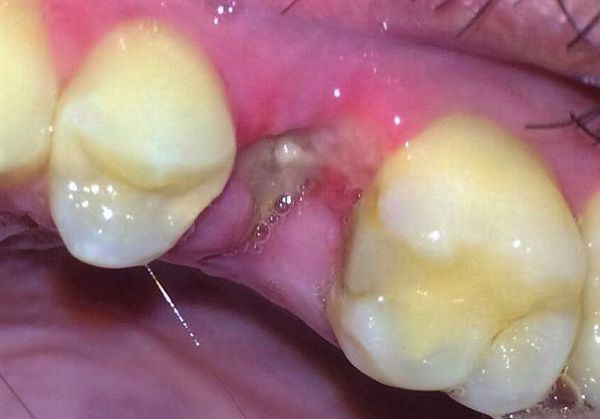

- Odsłonięty zębodół – brak skrzepu sprawia, że zębodół wygląda na pusty, a czasami widoczna jest odsłonięta kość. Może być pokryty szarawym nalotem, a otaczająca błona śluzowa staje się zaczerwieniona, obrzęknięta i bolesna przy dotyku.

Rozpoznanie alweolitis zwykle nie sprawia trudności, ponieważ schorzenie ma charakterystyczne objawy i rozwija się kilka dni po ekstrakcji zęba. Lekarz przeprowadza szczegółowy wywiad, a następnie dokładnie bada zębodół, oceniając jego wygląd, obecność skrzepu, zapach oraz stan błony śluzowej.